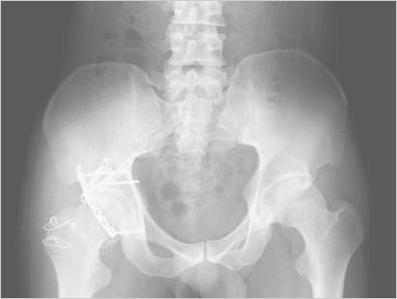

骨盤正面撮影 一般撮影室 Atwiki アットウィキ

骨盤レントゲンの読影 骨盤正面 寛骨臼の読み方を徹底解説 Gull Signとは 目指せスポーツドクター目指せスポーツドクター

骨盤骨折 日本整形外科学会 症状 病気をしらべる